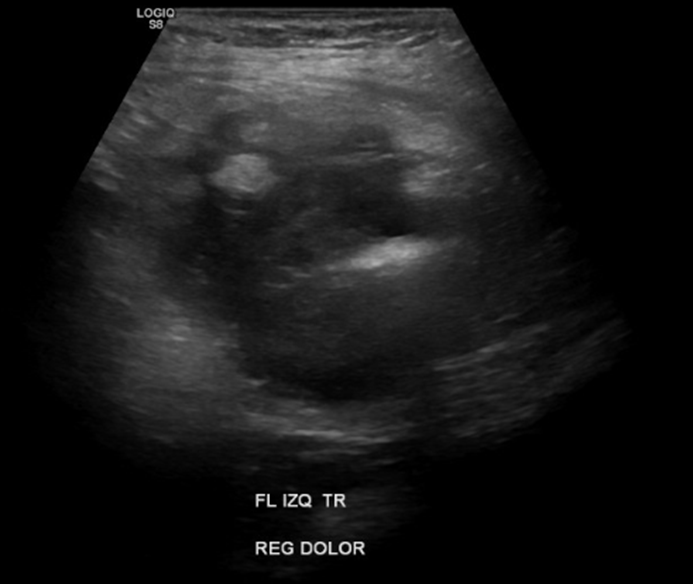

En Flanco izq en región de dolor, en relación a colon descendente, marcado engrosamiento de aspecto nodular, hipoecogénico y heterogéneo con moderada hiperemia al Doppler color y power. En signo de pseudoriñon, con leve aumento de la ecogenicidad de la grasa adyacente. Hallazgos sugerentes de adenocarcinoma

Se explora dirigidamente flanco izquierdo, donde en correspondencia con área de sensibilidad al paso del transductor, se identifica engrosamiento focal de la pared del colon descendente, con aumento de la vascularización al Doppler Color. Se esboza imagen de pseudoriñon, con aumento de la ecogenicidad de la grasa circundante.

Impresión: Hallazgos ecográficos compatibles con engrosamiento focal de la pared del colon descendente, con imagen de pseudoriñon. De acuerdo a criterio clínico se sugiere tomografía computada contrastada para descartar proceso proliferativo, así como sospecha de intususcepción en evolución.

• Signos de Pseudo Riñón: Los gases simulan ser el seno renal y el tumor el parénquima renal.